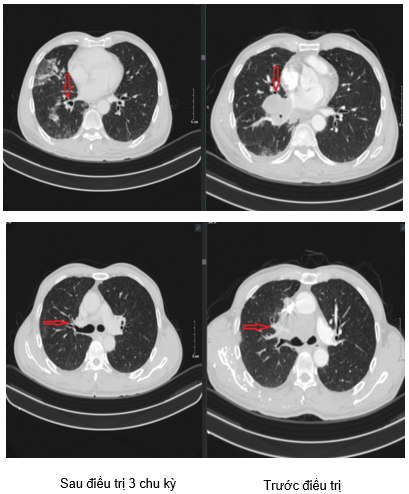

+Trung thất cân đối, vài hạch trung thất lớn nhất kích thước 17x8mm.

NHẬN XÉT: Như vậy chỉ sau 3 chu kì điều trị theo phác đồ Atezolizumab + Carboplatin + Etoposide, các tổn thương tại phổi, tổn thương di căn gan và các hạch khi được xác định trên các công cụ chẩn đoán hình ảnh đã có sự giảm kích thước đáng kể so với ban đầu, đồng thời khi định lượng CEA và Cyfra11-1 có xu hướng giảm từ sau chu kì thứ 3. Điều này chứng minh rằng phác đồ phối hợp trên là có hiệu quả đối với các bệnh nhân ung thư phổi tế bào nhỏ có di căn nhiều cơ quan như gan, hạch.